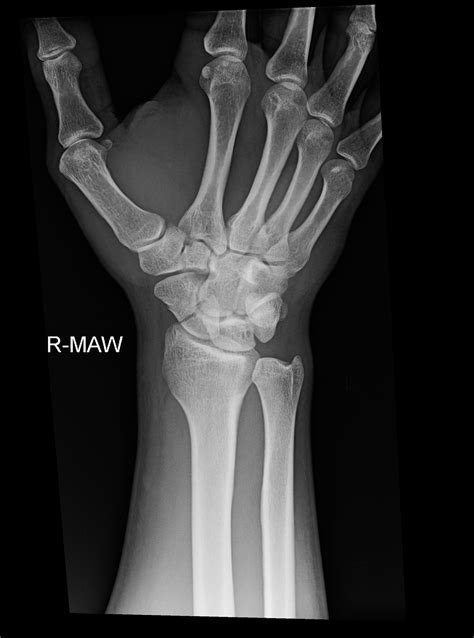

Diagnosis usually involves a physical examination followed by imaging. X-rays are the first line of defense; however, because scaphoid fractures can be hairline, they are not always visible on initial X-rays. If your doctor suspects a fracture but the image is clear, they may order an MRI or a CT scan to confirm the injury.

Surgery becomes necessary when the bone pieces are shifted (displaced) or when the fracture is located in a part of the bone with poor blood supply. During the procedure, an orthopedic surgeon will realign the bone fragments and secure them using metal hardware, such as a compression screw. This provides internal stability and often leads to a faster recovery time compared to long-term casting.

Because the scaphoid is susceptible to poor blood flow, there is a risk of a condition called avascular necrosis, where the bone tissue dies due to lack of blood. Another concern is non-union, where the bones fail to heal, leading to pain and weakness. If you notice a sudden increase in pain, numbness in your fingers, or if the swelling does not go down after several weeks, contact your specialist immediately to ensure your Scaphoid Fracture Treatment is still on track.